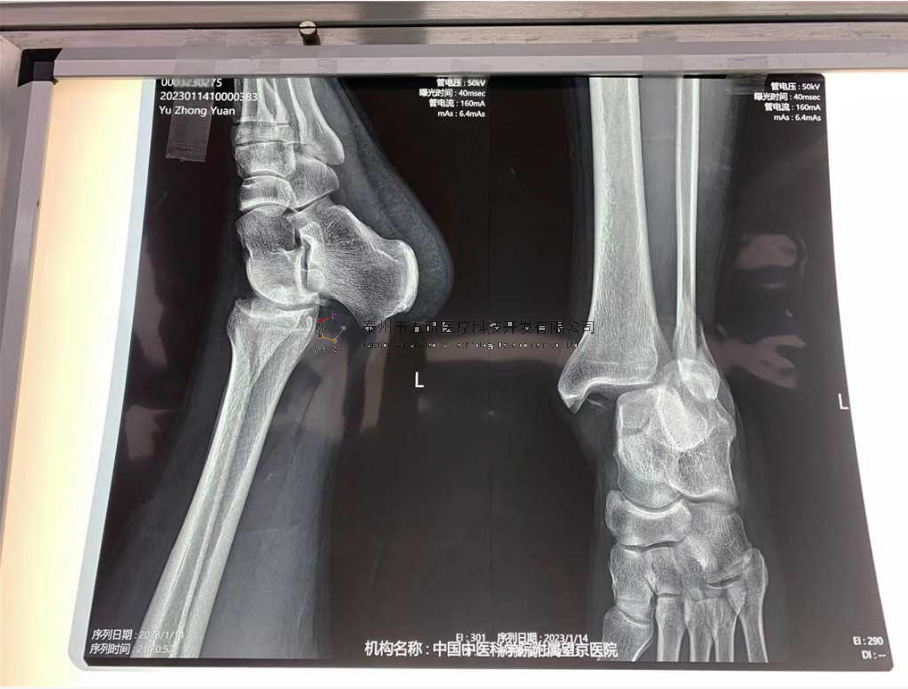

本病例由中國中醫(yī)科學院望京醫(yī)院骨關二提供(術者:支架主任蔣主任)

【基本資料】患者,男,41歲

本病例踝關節(jié)骨折。手術名稱:左踝關節(jié)骨折外固定支架手術

【治療前影像】